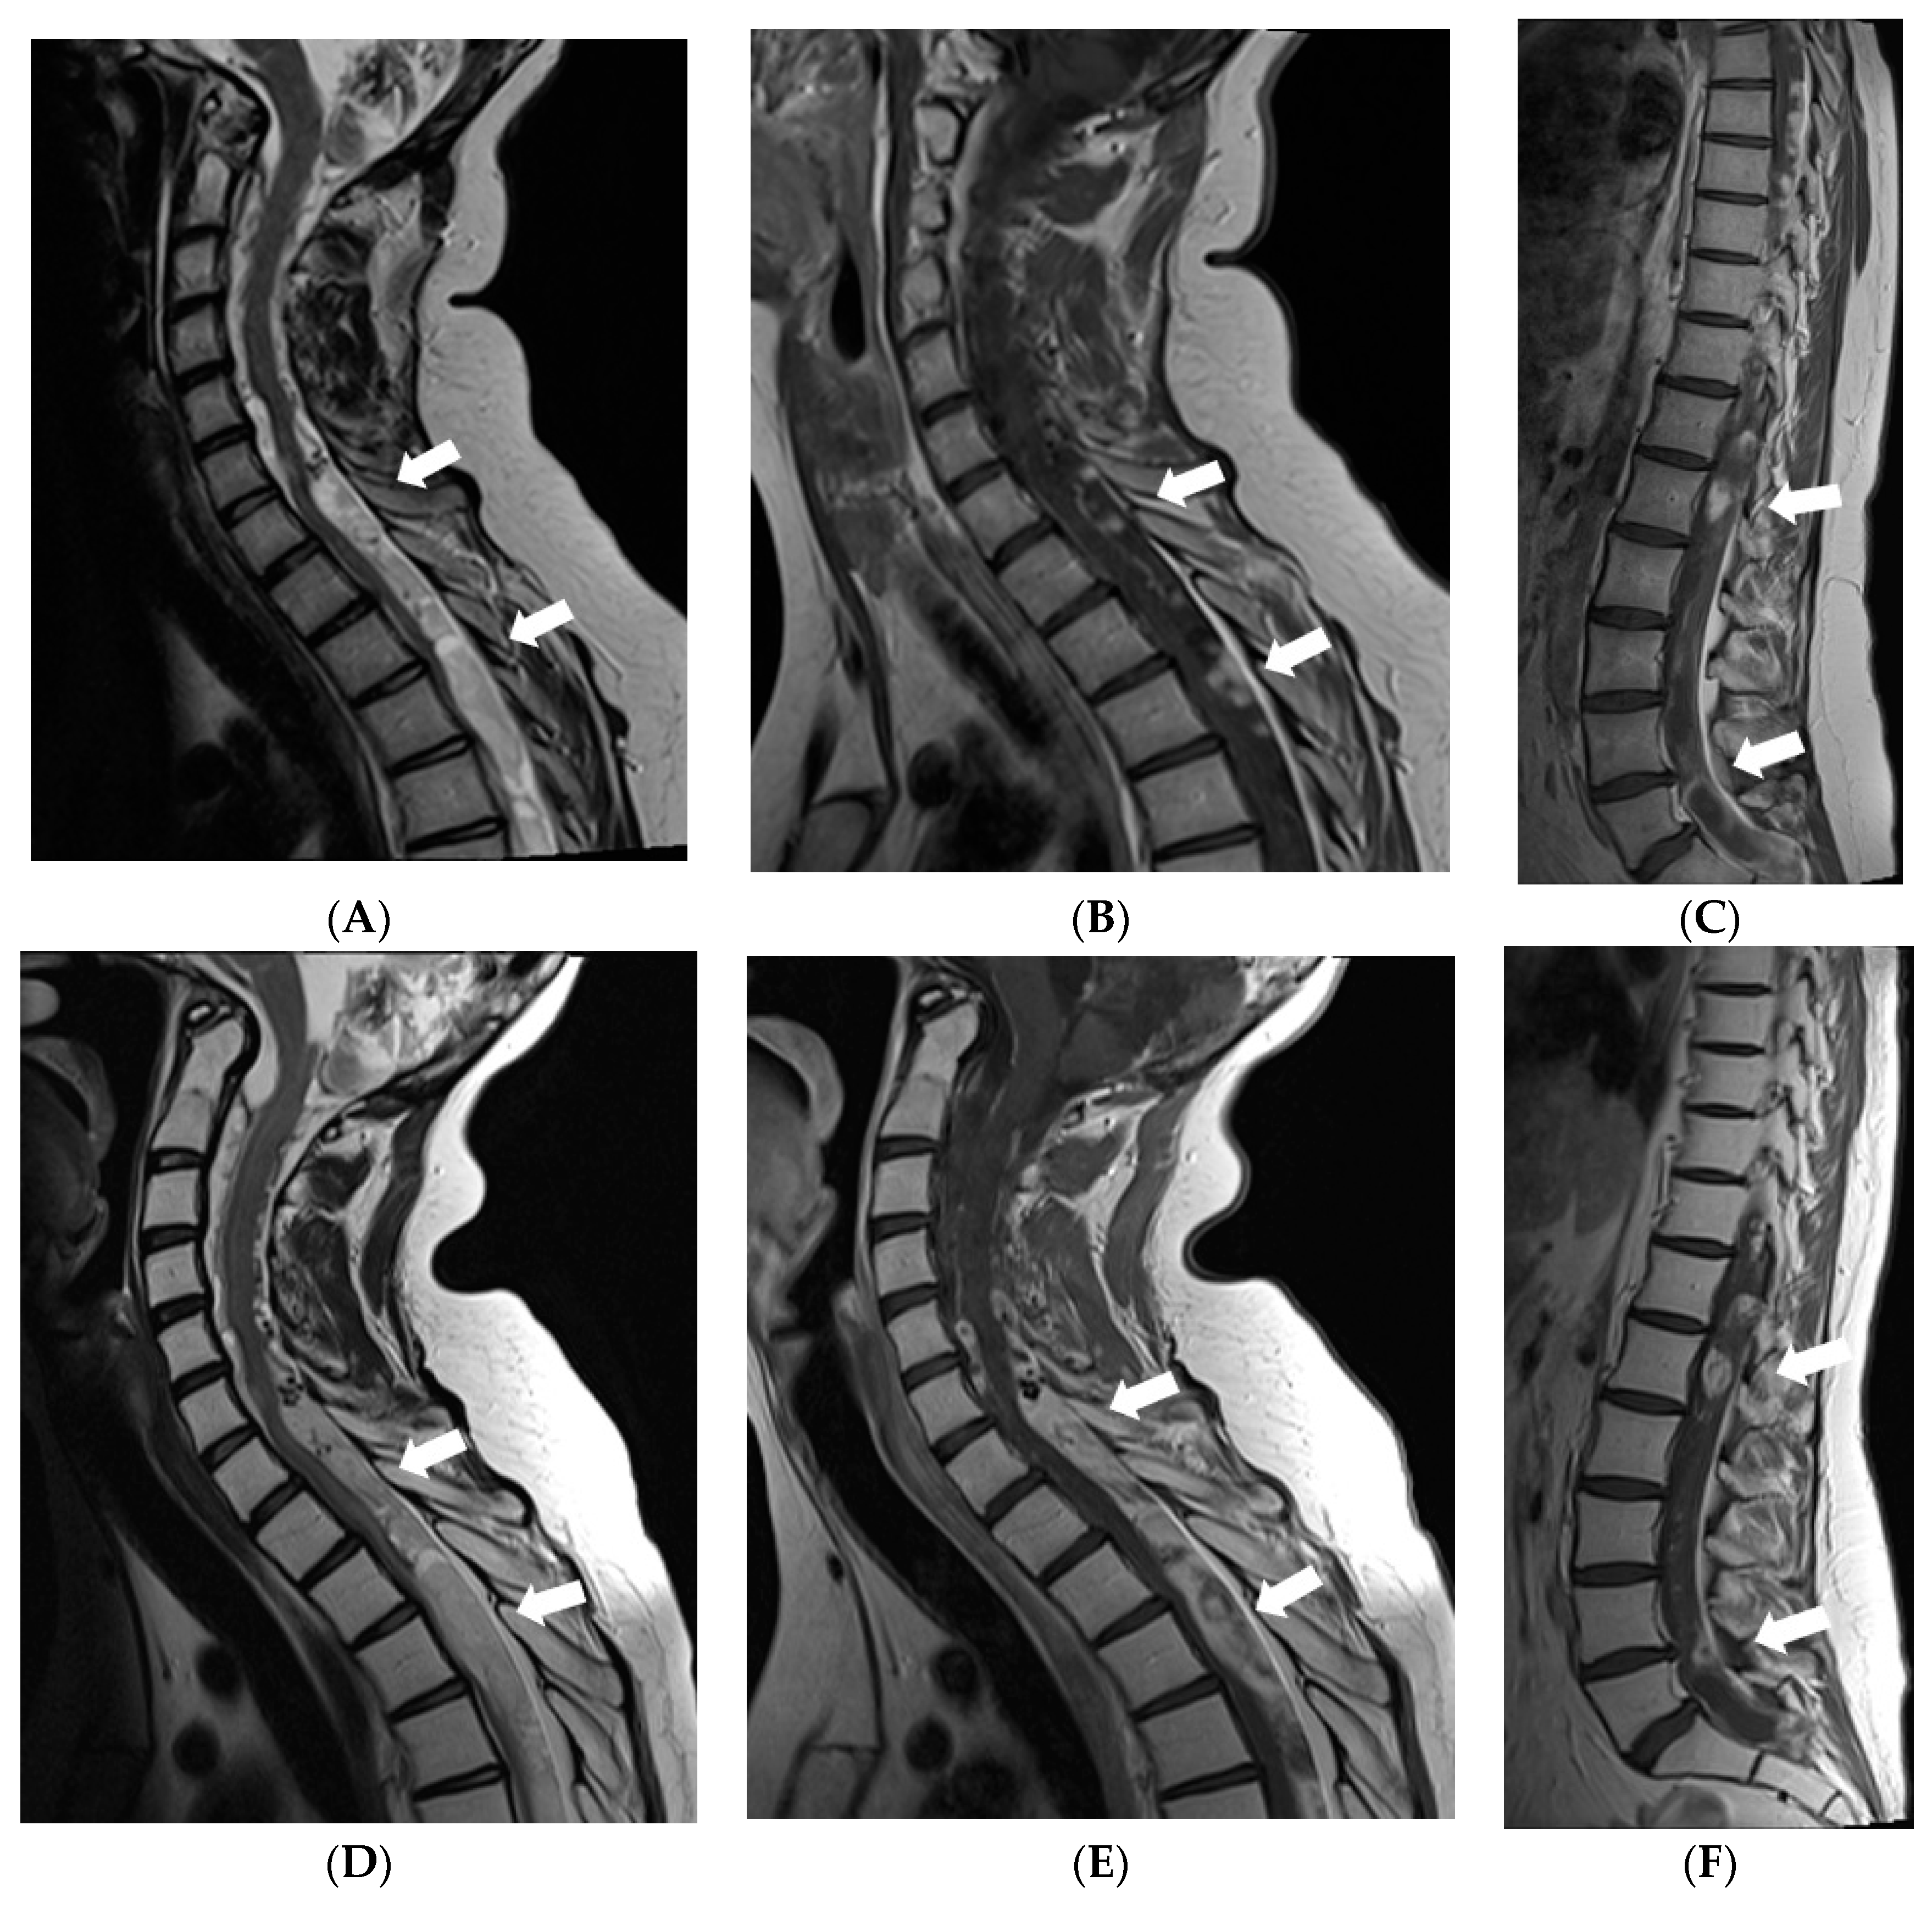

Due to impaired vision, further loss of hearing, and ability to walk, an MRI of the brain and spine was repeated in 2020. MR brain revealed residual changes—cystic leptomeningeal-subpial nodular lesions that were hypointense on T2W/FLAIR, and did not show contrast enhancement in the posterior fossa and along the basal cisterns, surrounding the brainstem, cranial nerves, and cerebellum. Imaging of spinal cord revealed cystic nodular lesions resembling those found in the brain and causing persistent, multisegmental spinal cord compression (Figure 6).

Figure 6.

Follow-up MRI of the brain and spinal cord 9 years after the onset of symptoms (November 2020): (A) Axial T2W/FLAIR, (B,C) and (D) sagittal T1W post-contrast images demonstrate residual non-enhancing cystic lesions in basal cisterns and posterior fossa surrounding brainstem and cerebellum. (D) Sagittal T1W post-contrast image shows diffuse atrophy of the cerebellum. (E,G,I) Sagittal T2W and (F,H,J) T1W post-contrast images of (E,F) cervical, (G,H) thoracic, and (I,J) lumbar spinal cord reveal diffuse intradural extramedullary mixed cystic and solid lesions that show medium contrast enhancement and slight compression of spinal cord at various levels.